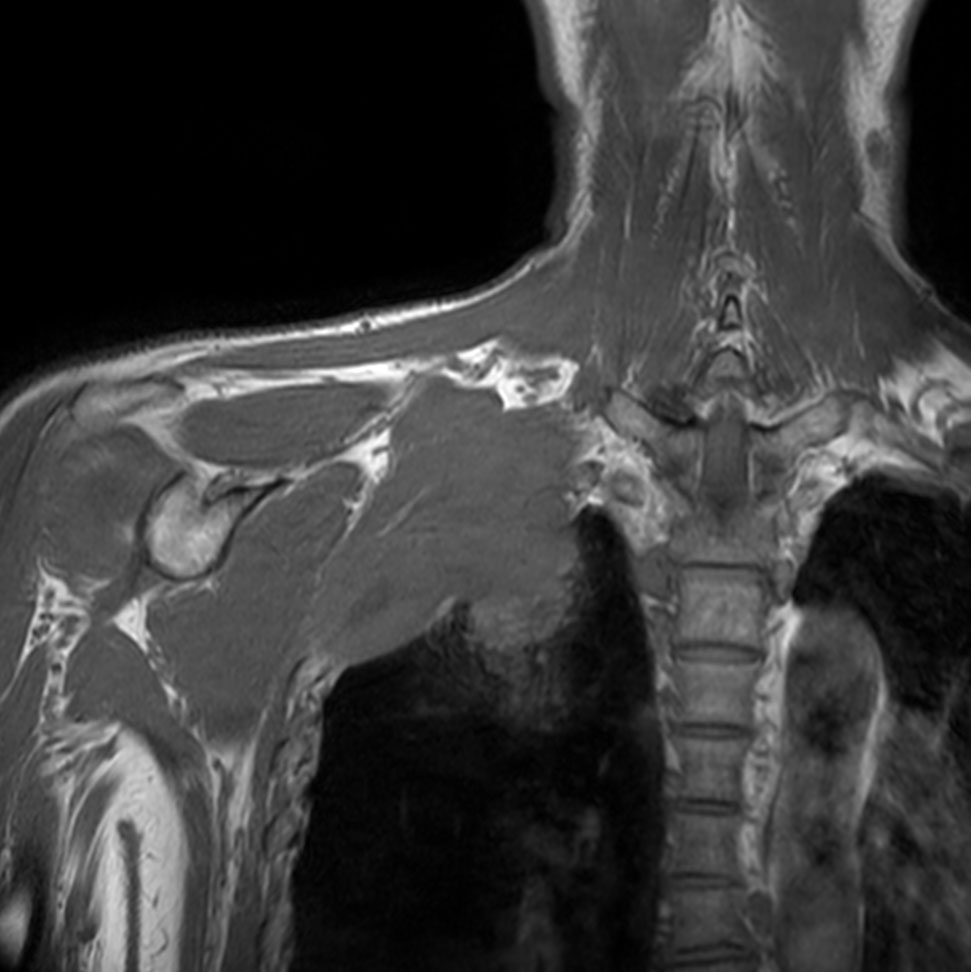

Coronal T1w TSE